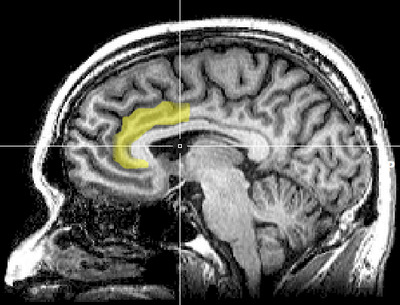

Cognitive dissonance produces a state of negative affect, which motivates the person to reconsider the causative behavior in order to resolve the psychological inconsistency that caused the mental stress.[88][89][90][91][92][93] As the afflicted person works towards a behavioral commitment, the motivational process then is activated in the left frontal cortex of the brain.[88][89][90][94][95]

The study Neural Activity Predicts Attitude Change in Cognitive Dissonance[97] (Van Veen, Krug, etc., 2009) identified the neural bases of cognitive dissonance with functional magnetic resonance imaging (fMRI); the neural scans of the participants replicated the basic findings of the induced-compliance paradigm. When in the fMRI scanner, some of the study participants argued that the uncomfortable, mechanical environment of the MRI machine nevertheless was a pleasant experience for them; some participants, from an experimental group, said they enjoyed the mechanical environment of the fMRI scanner more than did the control-group participants (paid actors) who argued about the uncomfortable experimental environment.[97]

The results of the neural scan experiment support the original theory of Cognitive Dissonance proposed by Festinger in 1957; and also support the psychological conflict theory, whereby the anterior cingulate functions, in counter-attitudinal response, to activate the dorsal anterior cingulate cortex and the anterior insular cortex; the degree of activation of said regions of the brain is predicted by the degree of change in the psychological attitude of the person.[97]

The Neural Basis of Rationalization: Cognitive Dissonance Reduction During Decision-making[32] (Jarcho, Berkman, Lieberman, 2010) applied the free-choice paradigm to fMRI examination of the brain's decision-making process whilst the study participant actively tried to reduce cognitive dissonance. The results indicated that the active reduction of psychological dissonance increased neural activity in the right-inferior frontal gyrus, in the medial fronto-parietal region, and in the ventral striatum, and that neural activity decreased in the anterior insula.[32] That the neural activities of rationalization occur in seconds, without conscious deliberation on the part of the person; and that the brain engages in emotional responses whilst effecting decisions.[32]

Emotional correlations

The results reported in Contributions from Research on Anger and Cognitive Dissonance to Understanding the Motivational Functions of Asymmetrical Frontal Brain Activity[100] (Harmon-Jones, 2004) indicate that the occurrence of cognitive dissonance is associated with neural activity in the left frontal cortex, a brain structure also associated with the emotion of anger; moreover, functionally, anger motivates neural activity in the left frontal cortex.[101] Applying a directional model of Approach motivation, the study Anger and the Behavioural Approach System (2003) indicated that the relation between cognitive dissonance and anger is supported by neural activity in the left frontal cortex that occurs when a person takes control of the social situation causing the cognitive dissonance. Conversely, if the person cannot control or cannot change the psychologically stressful situation, he or she is without a motivation to change the circumstance, then there arise other, negative emotions to manage the cognitive dissonance, such as socially inappropriate behavior.[89][102][100]

The anterior cingulate cortex activity increases when errors occur and are being monitored as well as having behavioral conflicts with the self-concept as a form of higher-level thinking.[103] A study was done to test the prediction that the left frontal cortex would have increased activity. University students had to write a paper depending on if they were assigned to a high-choice or low-choice condition. The low-choice condition required students to write about supporting a 10% increase in tuition at their university. The point of this condition was to see how significant the counterchoice may affect a person's ability to cope. The high-choice condition asked students to write in favor of tuition increase as if it were their completely voluntary choice. The researchers use EEG to analyze students before they wrote the essay, as dissonance is at its highest during this time (Beauvois and Joule, 1996). High-choice condition participants showed a higher level of the left frontal cortex than the low-choice participants. Results show that the initial experience of dissonance can be apparent in the anterior cingulate cortex, then the left frontal cortex is activated, which also activates the approach motivational system to reduce anger.[103][104]